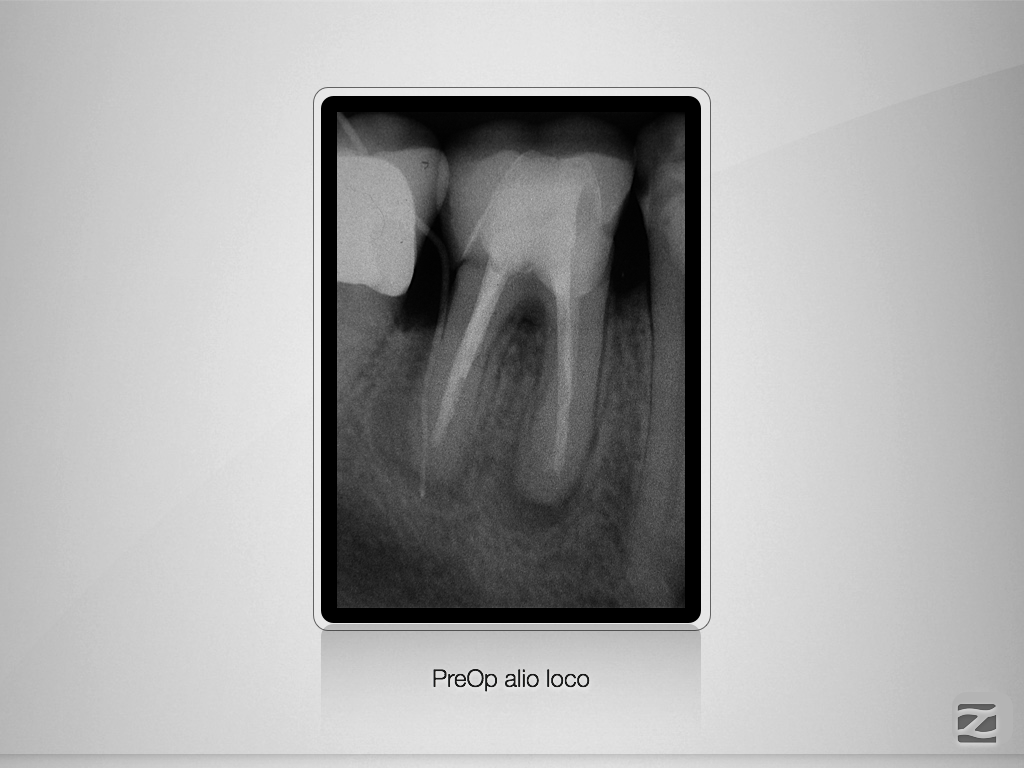

46D.001

8-Jahres-Recall